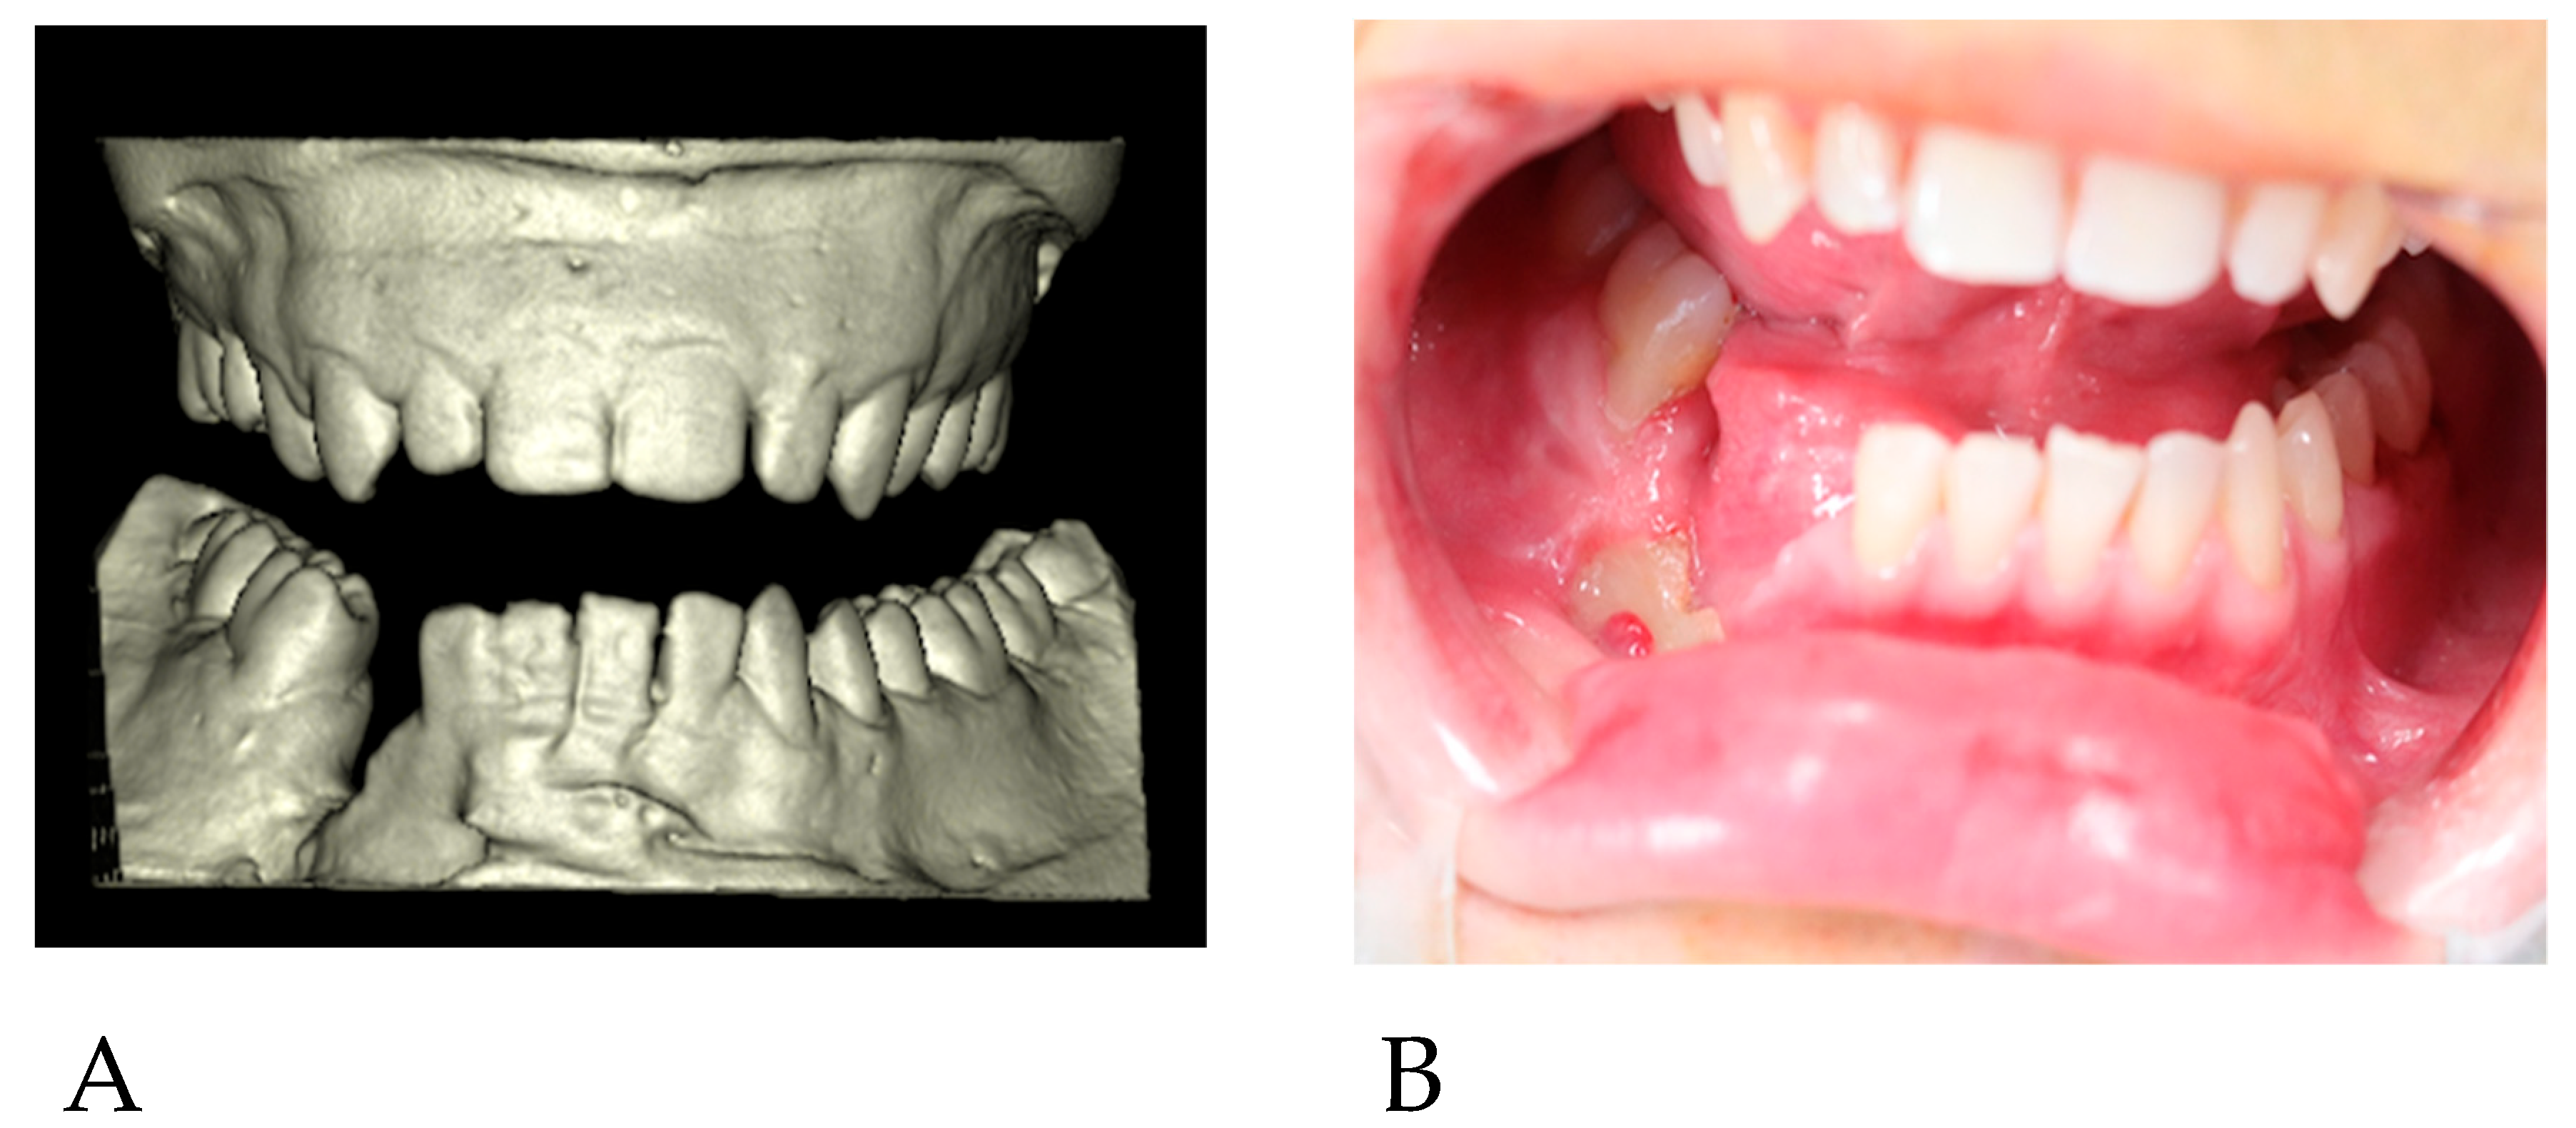

Parts of the necrotic bone were removed, and a swab was taken. After obtaining the results of antibiotic sensitivity testing conducted at the wound site, the patient was treated with targeted oral antibiotic therapy (clindamycin 300 mg 3 × 1; Clindamycin MIP 300®, MIP Pharma, Warsaw, Poland) for 14 days. During the follow-up visit, there was no inflammation, and the exposure site was clean (Figure 2B). Another facial CT scan was performed, and dental impressions were taken for the production of plaster models (Figure 2A). The patient was conscious, and no findings were noted in the oral cavity and nasopharynx. There were no palpable nodules in the patient’s head and neck area. The patient’s lab data and electrocardiogram showed no abnormalities. There was no history of surgical procedures prior to the trauma. Oral and written consent was obtained.

Figure 2. (A) 3D reconstruction of the plaster models. (B) Surgical site prior to surgery.